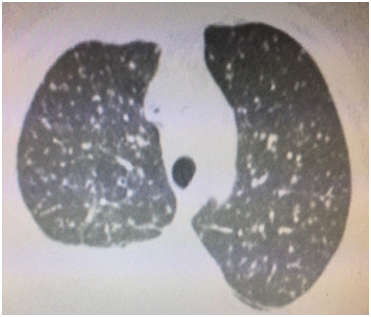

A 57 year old Caucasian female was admitted for dry cough, fever, loss of appetite and chest pain for three weeks. She had a history of tonsillectomy, ankylozing spondylitis, uveitis, pelvis fracture and tibia fracture. Her father died of colonic carcinoma. Her mother had hypertension and previous pulmonary tuberculosis. The patient was under treatment with certolizumab, methotrexate, and prednisolonefor ankylozing spondylitis and uveitis. Daily 300mg isoniazid was also given simultaneously with certolizumab for prophylaxis. Initial laboratory findings revealed WBC 8.2X103/mm3, hemoglobin 10.8g/dl, platelets 341X103mm3, lymphocytes 1.4X103/mm3, creatinine 0.74mg/dl, AST 18IU/L, ALT 18IU/Lmm3, LDH 167IU/L, albumine 3.56gr/dl, CRP 18.6 mg/dl, and calcium 9.1 mg/dl. ECG showed sinus ryhtm. Tuberculin test was negative. Chest x-rayshowed diffuse miliary nodules, alveolar infiltration in the right lower lobe, and right pleural effusion (Figure 1). Pleural protein 4.57g/dl, LDH 353U/L, and albumin 3.56g/dl. Pleural fluid had 1540cells/mm3 with a 74% lymphocyte ratio. Pleural fluid ADA was 114U/L (normal 0-40 U/L). The pleural fluid was exudative compatible with tuberculosis. Computed tomography of the thorax revealed diffuse miliary nodules, infiltration in the right anterior segment of the lower lobe, and right pleural effusion (Figures 2-4). Sputum stains was positive for acid-fast bacilli. Mycobacterium tuberculosis was isolated from the sputum culture. The final diagnosis was miliary tuberculosis associated with certolizumab occuring on the third month of treatment. The patient was commenced on pyrazinamide, isoniazid, rifampicine, and ethambutol treatment for tuberculosis while certolizumab treatment was stopped.

Figure 2 Coronal computed tomography revealing right lower anterior segmentinfiltration, right pleural effusion, and diffuse miliary nodules.